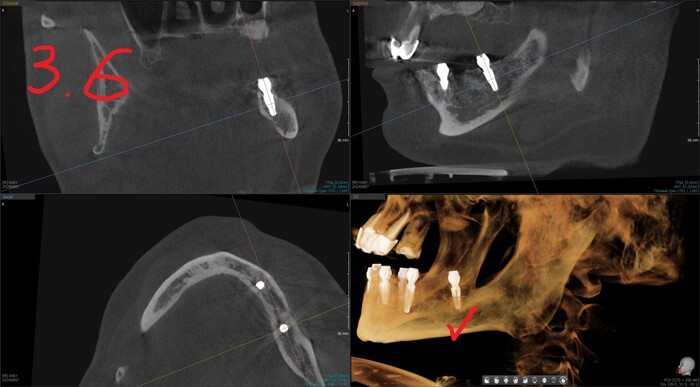

Результат такой - торки получены эталонные везде, кроме двух крайних имплантатов слева (3.4 и 3.6). Но не страшно, сверху зубов-антогонистов нет, нагрузки на протез не будет серьёзной. Да и "всё на 6" прощает подобное.

Позиция 4.6

Имплантолог видит, сколько мм можно докрутить безопасно для структур челюсти (нервов, сосудов). Делает дело.